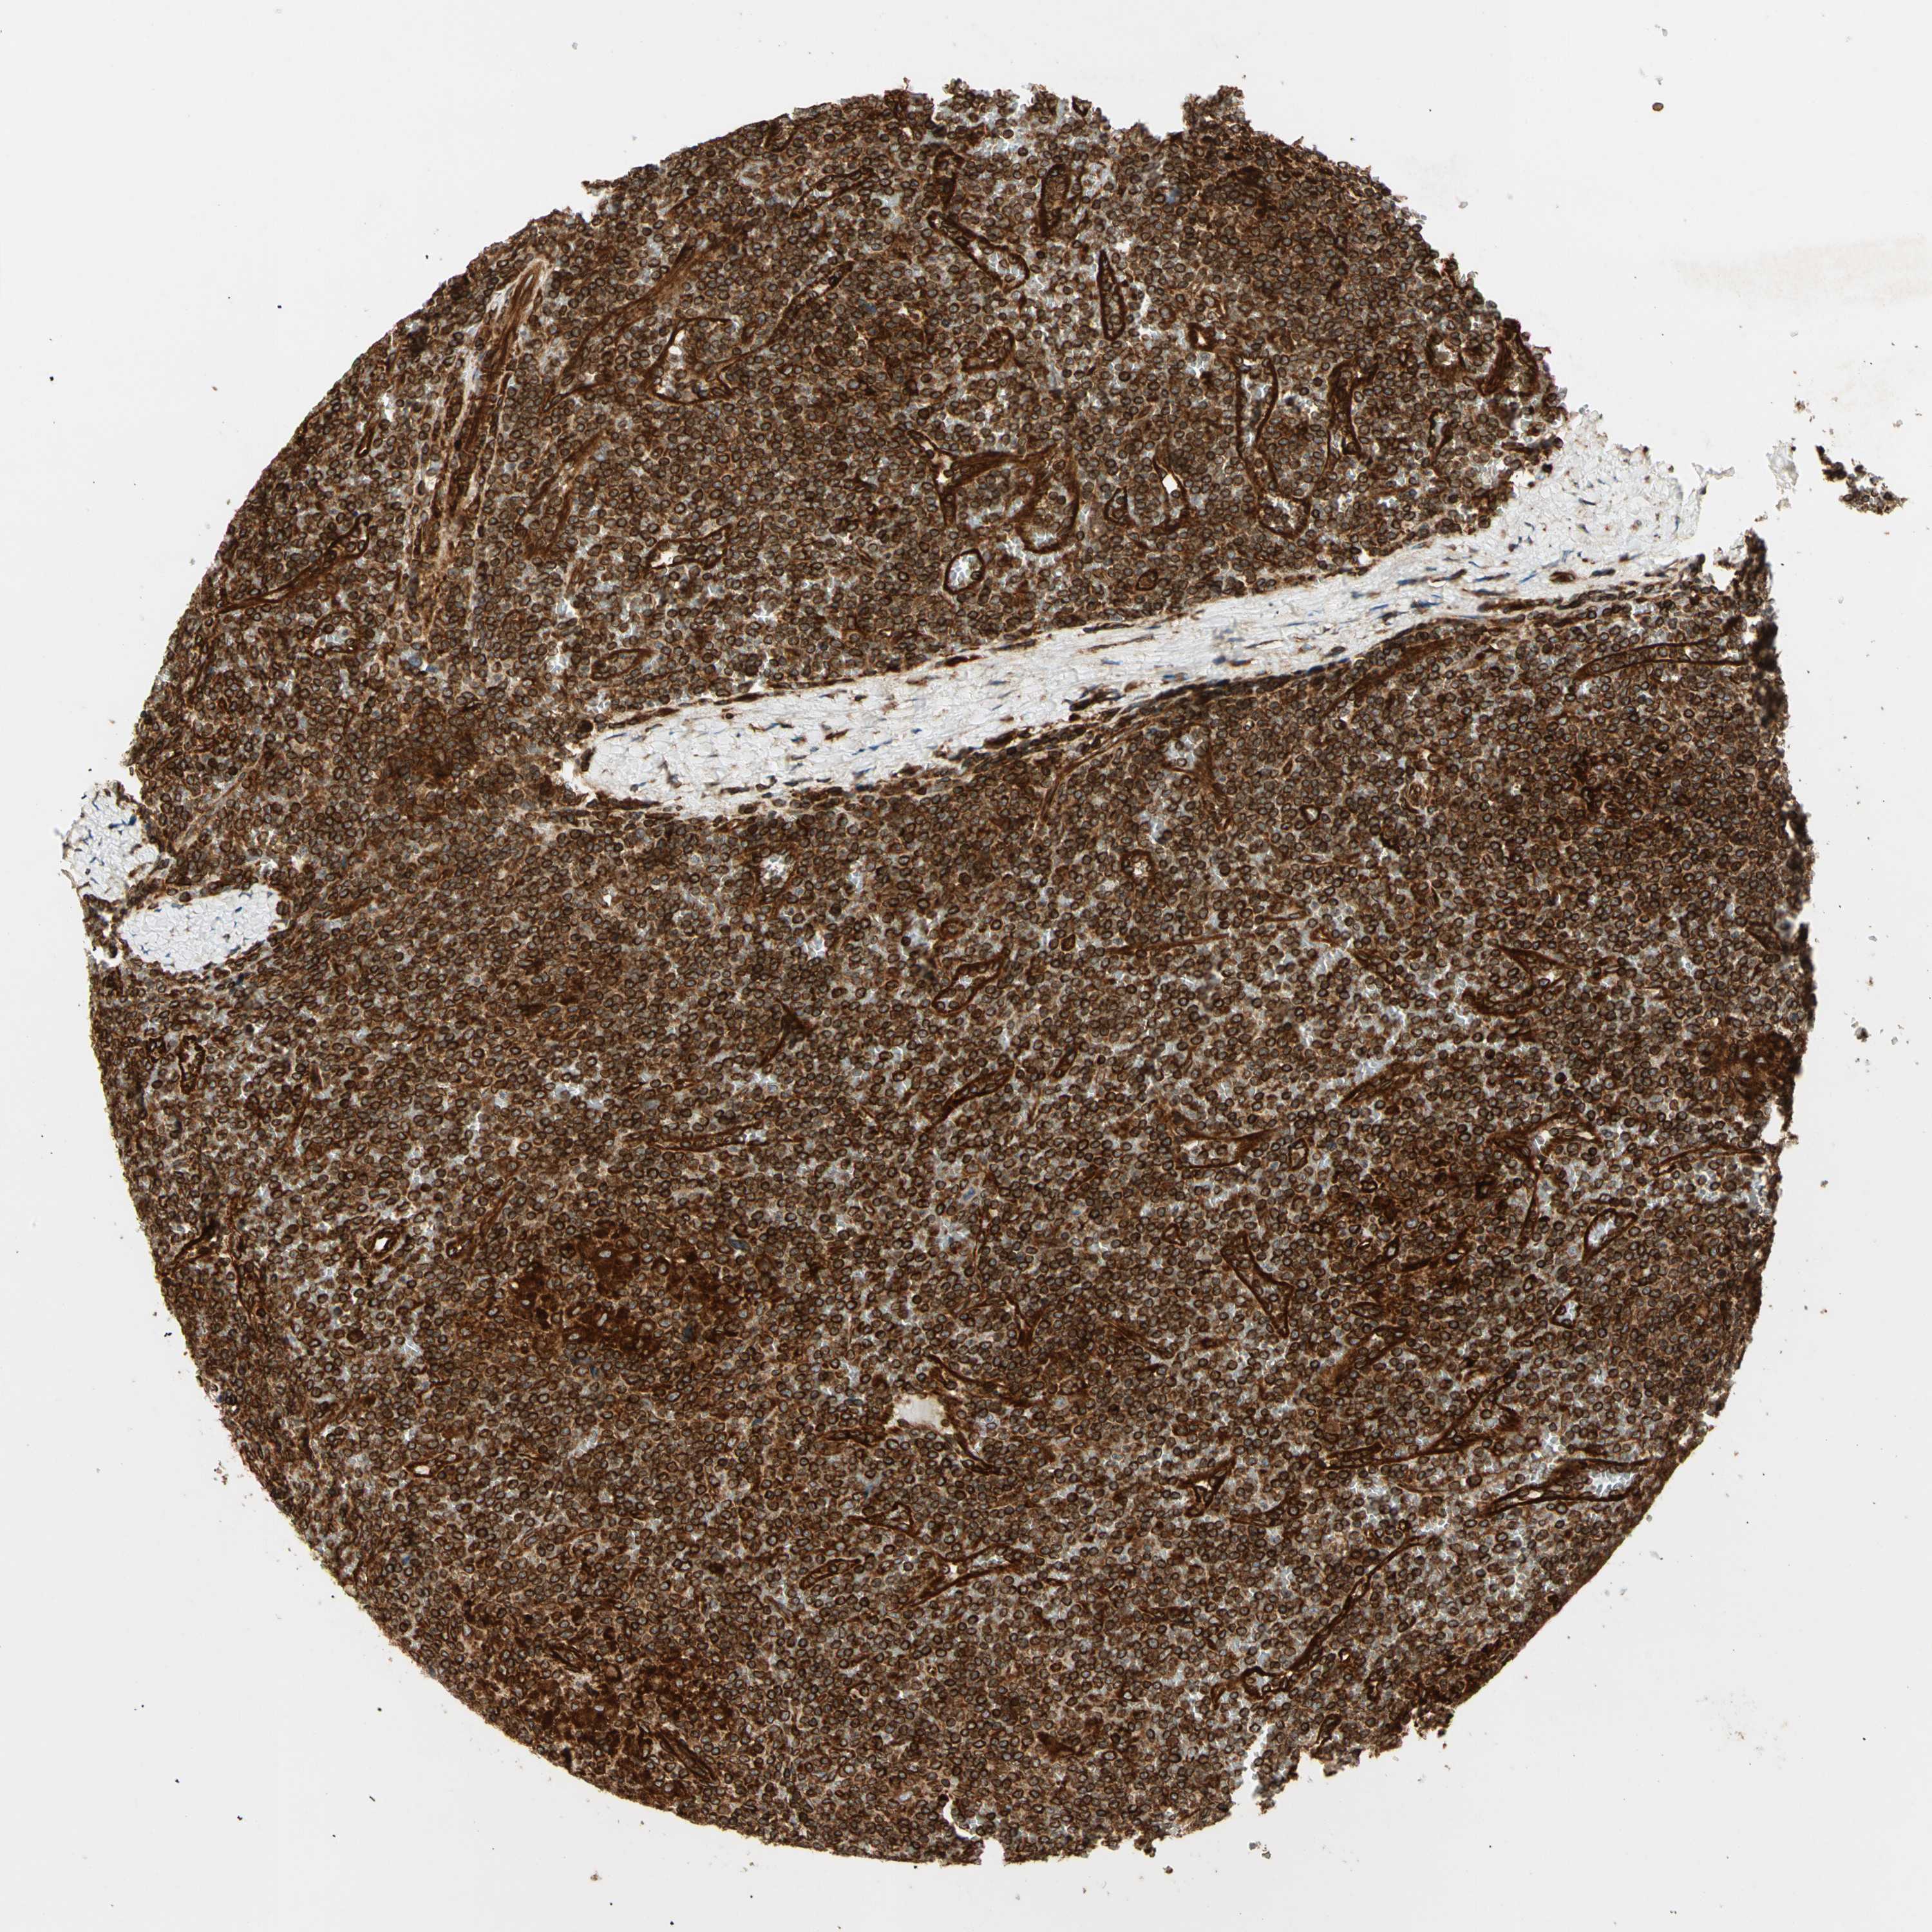

CANCER LYMPHOMA Show tissue menu

LYMPHOMA - Protein expressioni

A mouse-over function shows sample information and annotation data. Click on an image to view it in a full screen mode. Samples can be filtered based on level of antibody staining by selecting one or several of the following categories: high, medium, low and not detected. The assay and annotation is described here.

Each image is clickable and will lead to virtual microscopy that enables deeper exploration of all samples and also displays staining intensity scores, fraction scores and subcellular localization as well as patient and tissue information for each sample.

Antibody HPA007066

Staining

High

Strong

Moderate

Quantity

>75%

Location

Nuclear

Cytoplasmic/membranous

Cytoplasmic/membranous,nuclear

Hodgkin's disease, NOS

Malignant lymphoma, non-Hodgkin's type, Low grade

Malignant lymphoma, non-Hodgkin's type, High grade